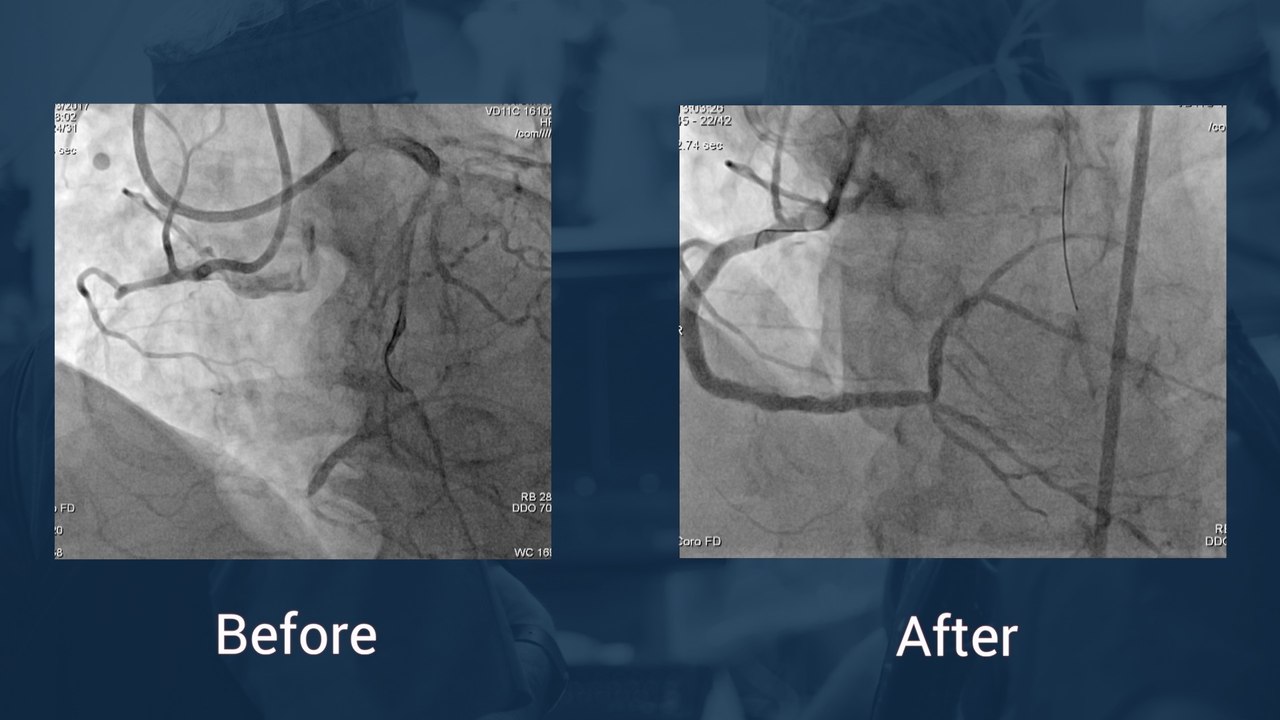

Very late BMS restenosis or neoatherosclerosis? Treatment with DES